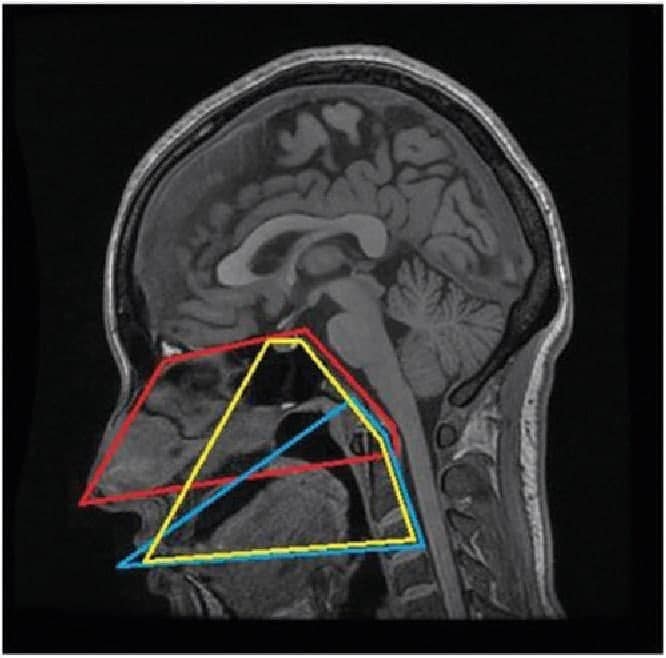

Энэхүү эмчилгээг хийснээр Монгол Улсад гавлын суурийн мэс засал эмчилгээний эхлэл болж, “АМНЫ ХӨНДИЙН ХҮРЦЭЭР” гавлын кливус орчмын хавдрууд түүнчлэн хүзүүний I, II нугаламын зарим хавдар, үрэвсэлт өвчин, хүн амын дунд тархмал тохиолддог хэрх өвчний үеийн хүзүүний шүдлэг сэртэнгийн эмгэгүүдэд эмчилгээ хийх шинэ арга нэвтрүүлж, нутагшуулахыг зорьж байна.